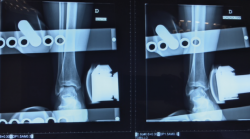

– Cajón anterior: paciente sentado con la rodilla en flexión. Aplicando rotación interna se testa el ligamento peroneo-astragalino anterior (PAA); con rotación externa valoramos la laxitud medial (frecuentemente asociada a dolor anteromedial)(Figura 2).

- Cajón anterior: positiva si existe una traslación anterior > 1 cm o una diferencia > 3 mm respecto al tobillo contralateral (Figura 4).

Figura 2. Maniobra del cajón anterior. Paciente sentado con la pierna colgando a 90°. El cajón anterior con tope óseo pone de manifiesto la insuficiencia del ligamento peroneo-astragalino anterior.

Figura 4. Radiografía del cajón anterior. El cajón anterior es positivo si existe una traslación anterior > 1 cm o una diferencia > 3 mm respecto al tobillo contralateral.